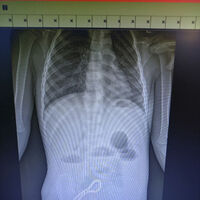

Ребенок попал в больницу с жалобами на проблемы с пищеварением. Медики предположили наличие в ЖКТ инородного тела, что подтвердил рентген.

«Было принято решение об операции. Мы провели минилапаротомию (хирургическое вмешательство, при котором через разрез передней брюшной стенки производится доступ к внутренним органам живота). И увидели, что магнитами, которые притянулись друг к другу, соединены петли кишки; в ее стенке отверстия. В ходе операции удалили все 30 магнитных бусин: 29 маленьких и одну большую», — рассказал хирург больницы Олег Ларькин.